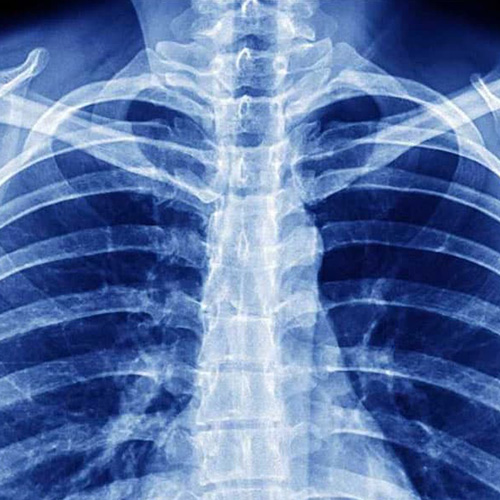

La valutazione dello Specialista in Pneumologia, ovvero il Medico specializzato nello studio e nella cura delle malattie dell’apparato respiratorio, si è tradizionalmente avvalsa di indagini sulla valutazione dei sintomi (soprattutto sul racconto della loro insorgenza ed evoluzione ovvero nell’analisi dei fattori di rischio: in primis tabagismo ed esposizione ad agenti tossici) accompagnata dal più classico degli esami clinici (ispezione, palpazione, ma soprattutto percussione e auscultazione alla ricerca di disturbi da escludere o monitorare a carico delle vie aeree).

La valutazione specialistica diventa anche importante per l’inquadramento di patologie non primitivamente respiratorie caratterizzate da sintomi come sensazione di oppressione al torace, difficoltà nella respirazione, affanno a riposo, tosse persistente, espettorazioni prolungate e/o con tracce di sangue, dolore toracico, apnee notturne.

Le patologie di interesse pneumologico sono fra quelle che rivestono una grande rilevo dal punto di vista socio sanitario, per la loro diffusione e spesso la prognosi infausta che, a livello oncologico, le caratterizza: broncopneumopatie croniche ostruttive, asma bronchiale e neoplasie polmonari.

Tutti gli esami ematici di routine possono essere utili per diagnosticare una malattia dell’apparato respiratorio. Ecco alcuni esami specifici per la diagnosi delle patologie respiratorie: esame colturale dell’espettorato: può essere utile, insieme alla diagnostica radiologica, nella diagnosi delle malattie infettive [...]